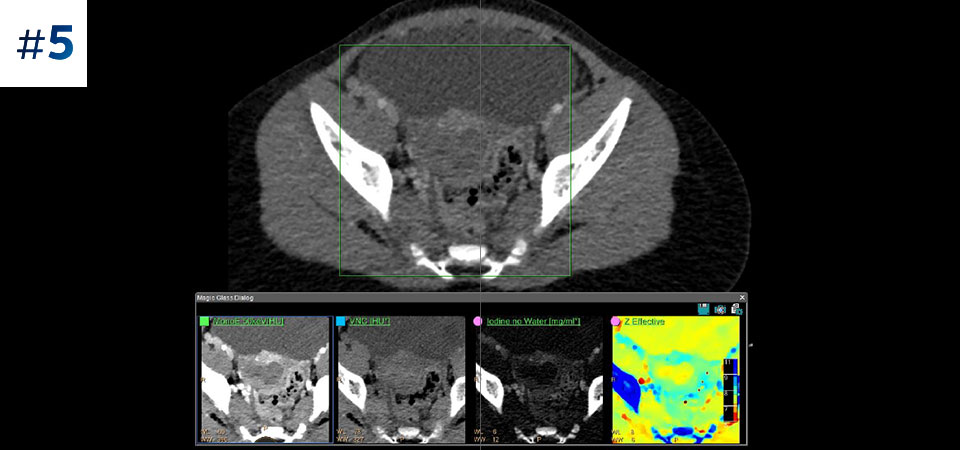

Neck mass